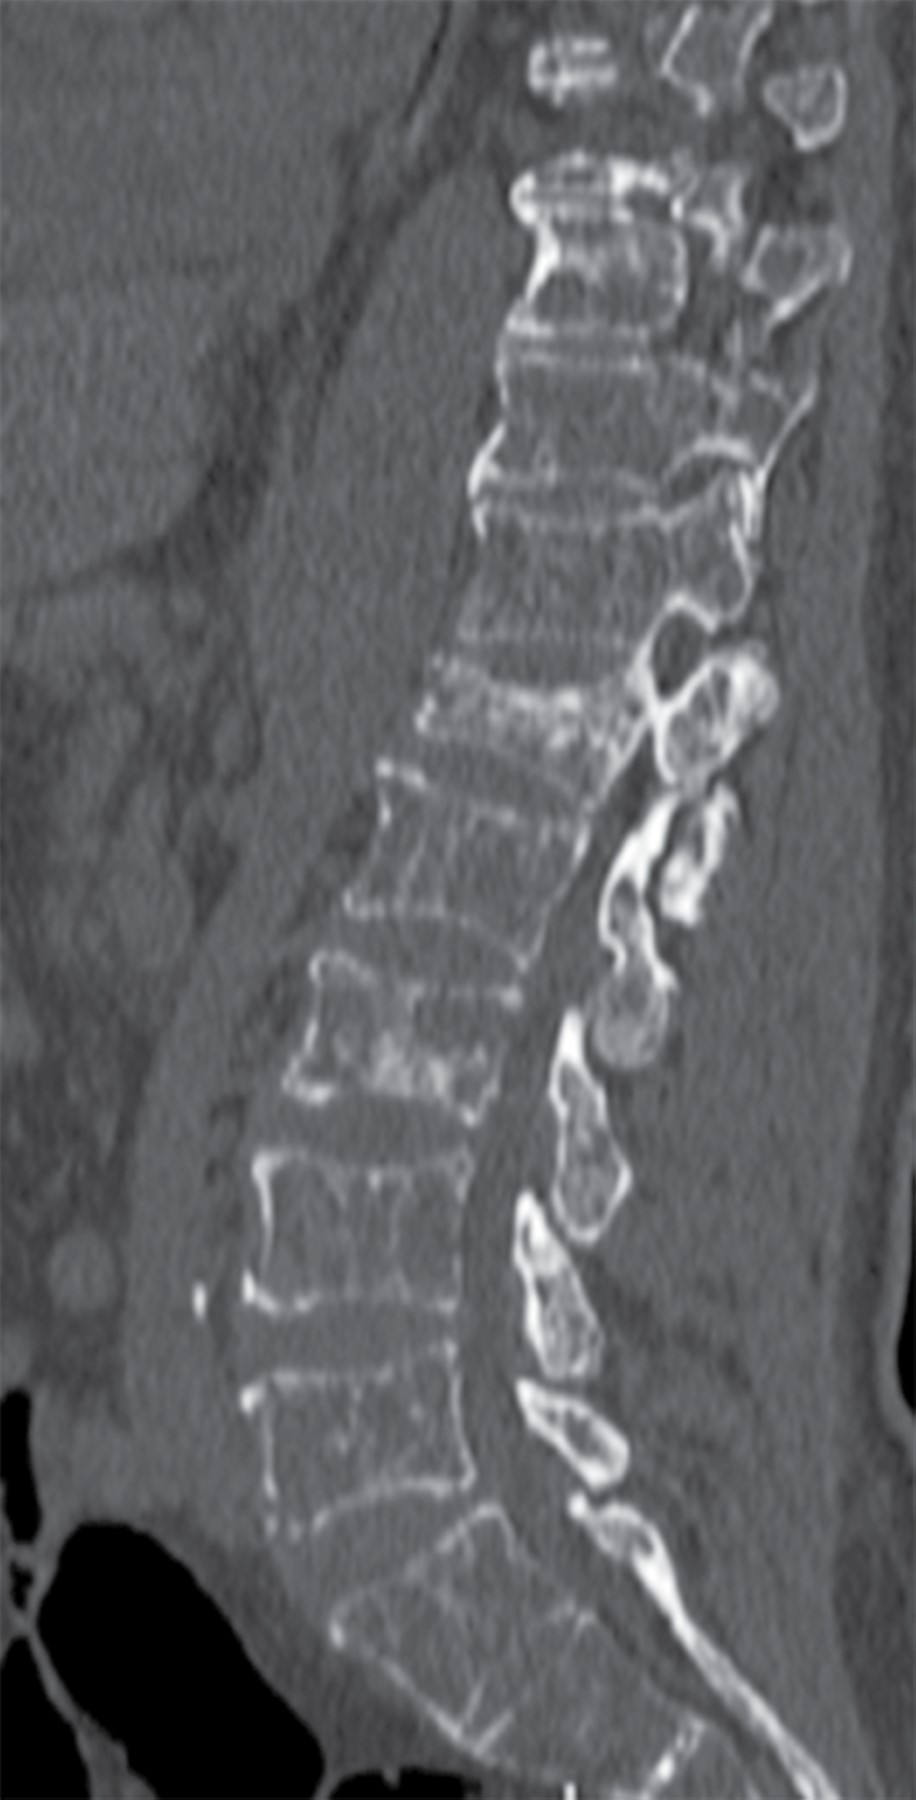

La distribución de las fracturas puede deberse a la infiltración de las células plasmáticas en el hueso trabecular similar al de la columna en comparación con el hueso menos hematopoyético como el cortical, lo que da como resultado la predilección de estas fracturas en regiones con mayor cantidad de trabéculas en su estructura (Figuras 1 y 2).11

Durante el seguimiento, se diagnosticaron 24 pacientes con alguna fractura asociada al mieloma múltiple, la localización de éstas se encontró con la siguiente distribución: columna en 39.4% (n = 13), húmero en 12.1% (n = 4), cadera en 9.1% (n = 3), fracturas con otra localización fuera del esqueleto axial en 9.1% (n = 3) y fémur en 3% (n = 1). Por otro lado, 27.3% de los pacientes no presentaron fracturas en el tiempo de seguimiento de este estudio.

Se realizó análisis de estudios de gabinete para encontrar datos radiográficos de la EOMM. De éstos, se excluyeron los hallazgos con trazo evidente de fractura, ya que varias características encontradas favorecerán la aparición de éstas, además de que denotan un estadio avanzado de la enfermedad. Al revisar los datos radiológicos de la enfermedad ósea encontramos que 30.3% (n = 10) de los pacientes presentaban lesiones líticas a nivel de la columna, la presencia de plasmocitoma se encontró en 18.8% (n = 8), lesiones líticas multinivel en 18.18% (n = 7) –estas lesiones incluyen más de un nivel vertebral, así como la inclusión de sacro o huesos largos–, destrucción vertebral en 6.1% (n = 2) y en 21.2% (n = 7) no se encontraron datos de enfermedad ósea del mieloma múltiple durante el seguimiento de los mismos.